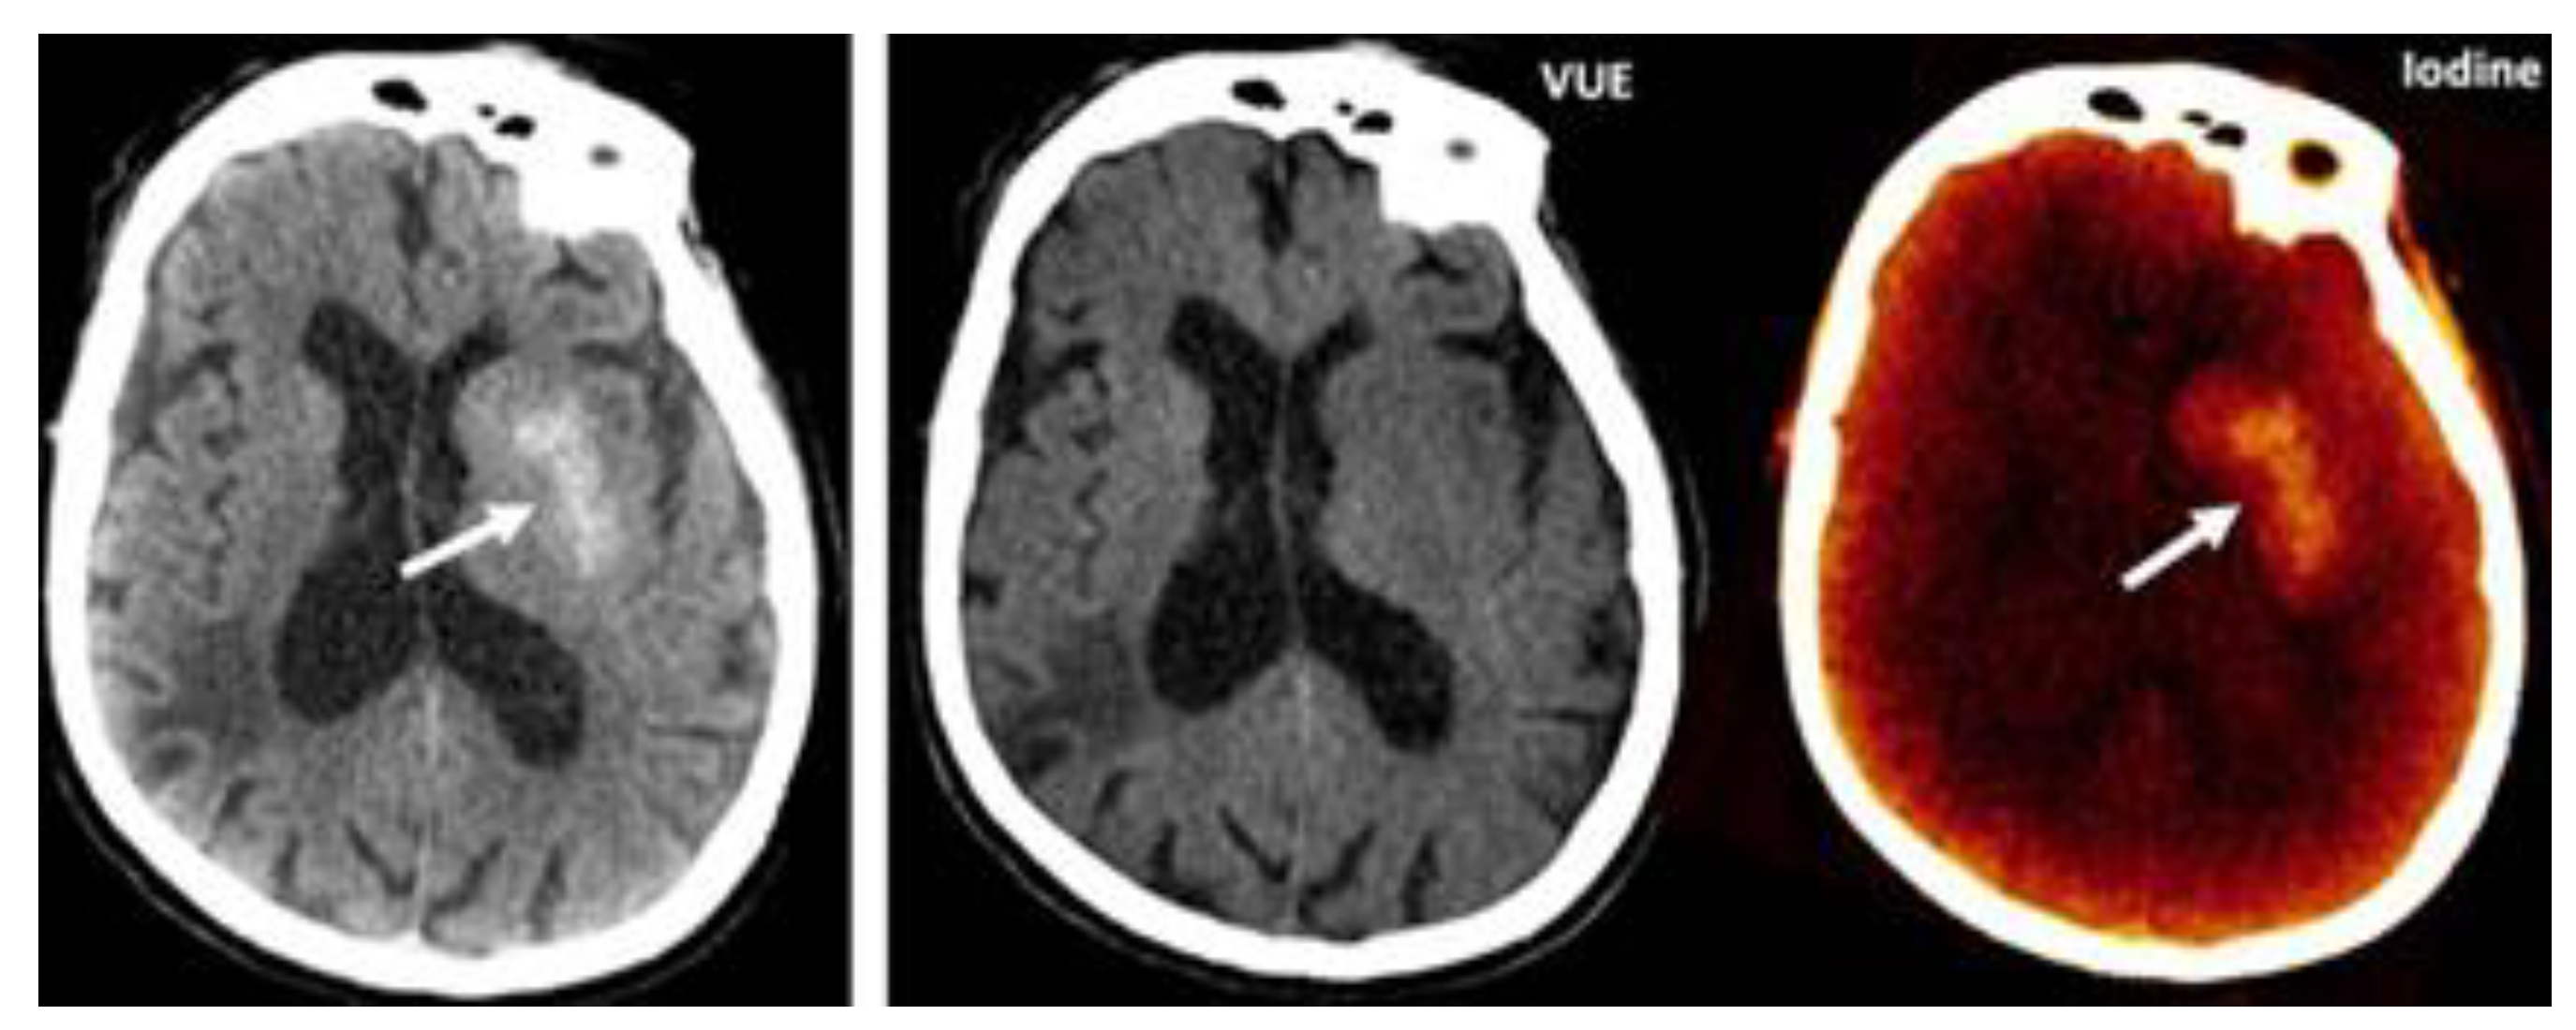

2.2.1.2. Material-Subtraction